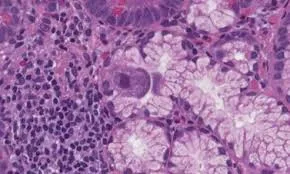

Cytomegalovirus (CMV) is a common herpesvirus that remains latent in most healthy individuals but can cause severe complications in immunocompromised patients and newborns. To ensure accurate detection and monitoring, cytomegalovirus pcr has become the gold standard in molecular diagnostics. By amplifying specific DNA sequences of the virus, PCR provides a level of sensitivity and specificity that traditional culture methods simply cannot match. This guide explores the mechanisms, clinical significance, and the technical advantages of utilizing PCR for CMV detection in modern medicine.

The primary objective of cytomegalovirus pcr is to detect the presence of CMV DNA in clinical specimens such as blood, urine, or saliva. For transplant recipients or HIV-positive patients, early detection of CMV reactivation is critical to prevent organ failure or systemic inflammation. Unlike antigen tests, PCR can detect extremely low copies of the viral genome, allowing clinicians to initiate antiviral therapy before the onset of severe symptoms. This proactive approach significantly improves patient survival rates and long-term recovery outcomes.